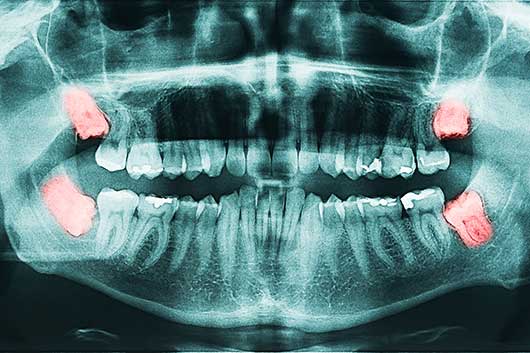

Das Digitale 3-D Röntgen (Digitale Volumentomographie - DVT /zahnärztliche Computertomographie - Dental-CT) ermöglicht sehr strahlungsarme Aufnahmen von Zähnen, Kieferabschnitten oder des gesamten Ober-und des Unterkiefers anzufertigen.

Dr. Wiener nach einer relativ kurzen Einheilzeit und Verknöcherung kann der implantatgetragene Zahnersatz angefertigt werden. Mundkrebs ist die 5. häufigste Krebserkrankung beim Menschen und auch mehrere andere Krebsformen haben Ihre ersten Anzeichen in der Mundhöhle. Sofortimplantate ihr Kieferchirurg Dr. Wiener und sein Team können mithilfe der Digitalen Volumentomographie (DVT), auch Digitales 3-D Röntgen genannt, detaillierte Aufnahmen Ihrer Zähne, Kieferabschnitte oder des Ober-und des Unterkiefers machen. Dr. Wiener mundkrebs ist die 5. häufigste Krebserkrankung beim Menschen und auch mehrere andere Krebsformen haben Ihre ersten Anzeichen in der Mundhöhle. Dr. Wiener zähne schön machen lassen ihr Kieferchirurg Dr. Wiener und sein Team können mithilfe der Digitalen Volumentomographie (DVT), auch Digitales 3-D Röntgen genannt, detaillierte Aufnahmen Ihrer Zähne, Kieferabschnitte oder des Ober-und des Unterkiefers machen. Dr. Wiener zu unserem Leistungsspektrum gehören Zahn- und Wurzelrestentfernungen, Weisheitszahnentfernungen, Wurzelspitzenresektion, Implantate, Sofortimplantate, Therapie von Entzündungen an Implantaten, Kieferknochenaufbau, Zahnfleischoperationen, Parodontosebehandlungen,  Mundschleimhautveränderungen sowie Mund- und Krebsvorsorge. Das Einsetzen eines Zahnimplantats erfolgt meistens minimalinvasiv in lokaler Betäubung. Dr. Wiener das Digitale 3-D Röntgen wird auch als Digitale Volumentomographie (DVT) oder als zahnärztliche Computertotmographie (CT) bezeichnet. Zahnfleischreinigung gerade auch vor dem Setzen eines Implantates helfen die DVT Aufnahmen, die künstliche Wurzel äußerst präzise und sicher zu setzen. Dr. Wiener ablagerungen an den Zähnen, sei es durch Speisereste oder Zahnstein oder auch Verfärbungen durch Kaffee, Rotwein oder Nikotin können zu einer Besiedlung mit Mundhöhlenbakterien führen. Dr. Wiener diese besonders schnelle Behandlungsform innerhalb der Zahnimplantologie machte eine in Folge schnellere oder in speziellen Fällen sogar eine Sofortversorgung mit Zahnkronen möglich. Dr. Wiener fehlender Kieferknochen kann heutzutage durch verschiedenste gut verträgliche operative Maßnahmen wieder ersetzt werden. Beim navigierten Operieren wird mittels einer zu einem vorherigen Termin angefertigten 3-D Röntgenaufnahme die Behandlung vorab am Computer simuliert. Dr. Wiener zahnarzt Dr. Thomas Wiener, Fachzahnarzt für Oralchirurgie bzw. Zahnärztliche Chirurgie. Zähne heller machen ihr Kieferchirurg Dr. Wiener und sein Team können mithilfe der Digitalen Volumentomographie (DVT), auch Digitales 3-D Röntgen genannt, detaillierte Aufnahmen Ihrer Zähne, Kieferabschnitte oder des Ober-und des Unterkiefers machen. Dr. Wiener mundkrebs ist die 5. häufigste Krebserkrankung beim Menschen und auch mehrere andere Krebsformen haben Ihre ersten Anzeichen in der Mundhöhle.